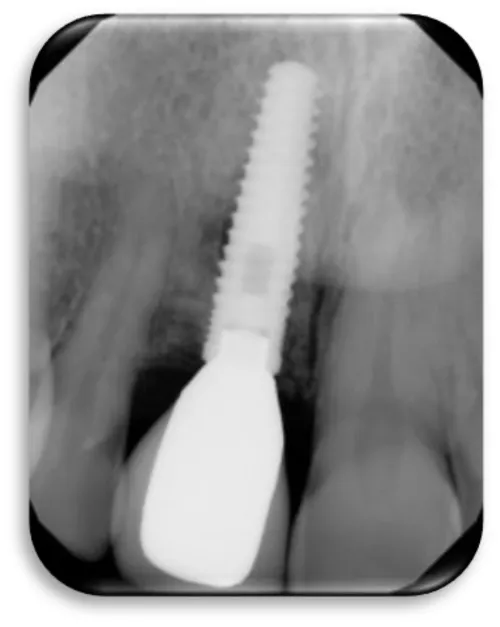

The first patient was at the age of 48 with male gender and generally with good health. There are no contraindications to make oral surgery. The patient is not allergic to any medication. A dental implant was placed 12 months ago (Figures 11,12), the dental implant’s position was 46. The implant was 4.1 mm in diameter and 12 mm in length. The patient has peri-implantitis, a RTG intraoral radiography image was recorded and marginal bone resorption was observed. The depth of the gingival sulcus was 10mm. Dehiscencia was seen in the patient from the buccal side of the implant (Figure 13). The bone defect was closed with a bone graft (Figures 14-16).

Woman at aged 37 year age, in good health condition and without any systemic diseases, allergic to penicillin came for prosthetic rehabilitation. She was without second premolar and first molar in the lower right quadrant. The patient was provided with dental implants at 45 and 46 (Figures 17-19). After a month on a 45-implant, retrograde peri-implantitis appeared. In chronological order, X-ray images are shown on figures from 17 to 20.